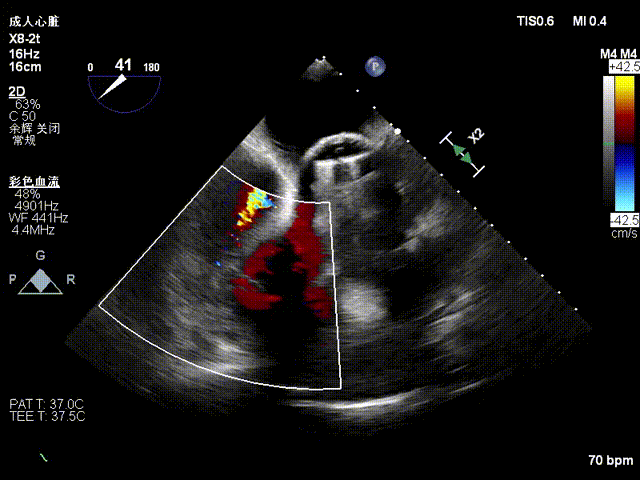

超声心动图:三尖瓣瓣环显著扩张(平均径42mm),瓣叶对合不良,TR 4+;肺动脉收缩压 58mmHg;左心室射血分数(LVEF)54%;人工二尖瓣功能未见异常。

1. 术中基线评估三尖瓣反流程度

1. 瓣环面积由18.7降至11.9,瓣环面积减少36%。

2. 术前反流4+降至1+。